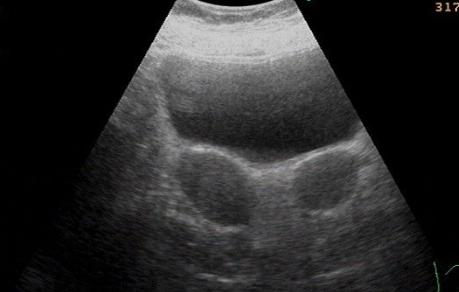

而患者可无任何症状,一般在人工流产、产前检查,甚至分娩时偶然发现。经B超检查,可使双子宫“真相大白”。该病一般不影响结婚和生育,如双子宫合并阴道纵隔,婚后可出现*交性**障碍或*交性**痛,应及时做手术切除纵隔。

双子宫病人在决定怀孕前,可以先通过检查判断左右两个子宫哪个是“好”子宫,哪个是“坏”子宫,然后再通过B超对卵巢的排卵情况进行监测。如果左侧子宫发育良好,那么就可以在B超监测显示左侧卵巢排卵时怀孕。这样就可以避免胎儿着床在发育不良的子宫里,影响胎儿的正常生长了。